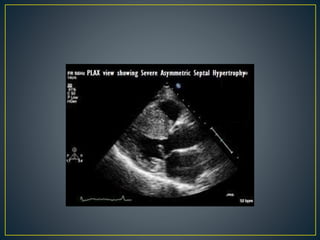

• Family history of HCM

• Asymmetry

• Right ventricular hypertrophy

• Late gadolinium enhancement at the RV insertion points or

localized to segments of maximum LV thickening on CMR

• Maximum LV wall thickness ≥15 mm (Caucasian); ≥20 mm

(black)

• Severe diastolic dysfunction

• Marked repolarization abnormalities, conduction disease or Q-

waves on 12 lead ECG